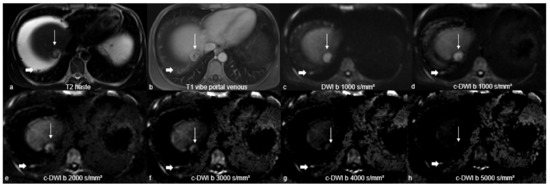

| Imaging Characteristics | DWI | c-DWI b 1000 | c-DWI b 2000 | c-DWI b3000 | c-DWI b 4000 | c-DWI b 5000 |

| c-DWI derived from DWI b 800-images | ||||||

| Volume cm³ [IQR] | 1 [1–7.5] | 1 [1–6.5] | 1 [0–6] | 1 [0–6] | not measurable | not measurable |

| p-value (comparison with DWI b 800-images) | 0.766 | 0.062 | 0.125 | |||

| c-DWI derived from DWI b 1000-images | ||||||

| volume cm³ [IQR] | 7 [1–26] | 6 [1–26] | 6 [1–83] | 7 [1–70] | not measurable | not measurable |

| p-value (comparison with DWI b 1000-images) | 0.102 | 0.021 | 0.051 |